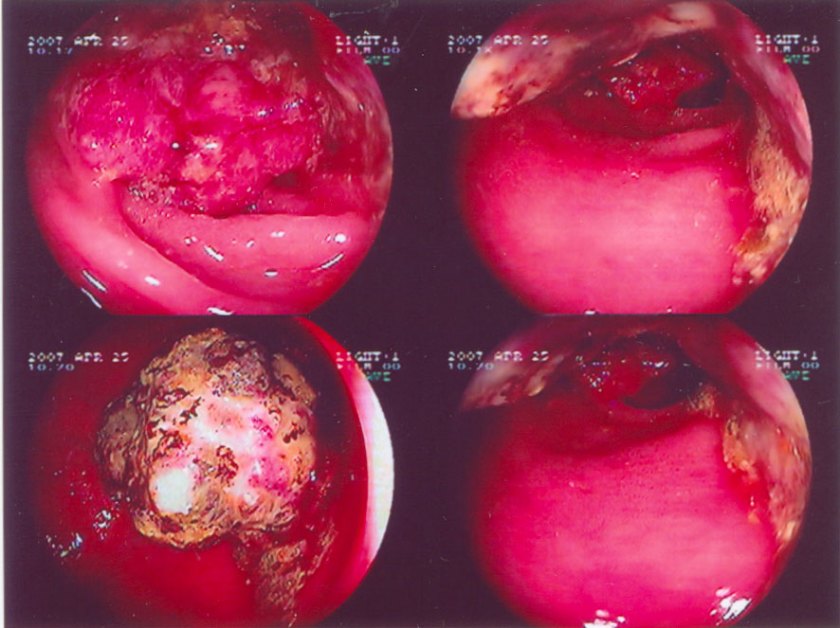

At the end of April 2007, she kept complaining of stomach discomforts, bloatedness and loss of appetite. She saw a Gastro-specialist and the diagnosis was H. pyroli infection and she was given antibiotic treatment. Unexpectedly, an X-ray test was also done and her lung was found abnormal. She did a CT scan and blood test including tumor markers on that same day. The results showed a possibility of lung cancer. One week later she did a lung biopsy. The result showed that the lung tumor mass was a moderately differentiated adenocarcinoma. However, she didn’t have breathing problems or coughs at that time.

She was then referred to an oncologist at the same hospital. My mum is an Asian woman with non-smoking history and the tumor type is adenocarcinoma. Hence she falls into the category that may respond well to a new targeted drug (Tyrosine Kinase inhibitor) called Iressa. The doctor said we can monitor her progress using CA15.3, the tumor marker with highest titer when first found (5147 on 24 April 2007).

After one month of taking Iressa, her CA15.3 went down to 367 (on 28 May 2007). On 30 July 2007, it declined further to 68.  We were so happy that the drug worked so well. A CT scan showed that tumor had shrunk (August 2007). At the forth month, the CA15.3 raised to 154 (on 27 August). The doctor was a bit worried but mum continued taking Iressa. A month later the marker rose to 713 (on28 September 2007). A CT scan showed more shadow in the lung compared to scan done in August 2007. She did a brain CT scan for the first time and some metastases were found in the brain and bones but the lesions were small.

My mother started taking another targeted drug called Tarceva (works on similar mechanism but seemed to be more effective). She had side effects like rashes, dry skin and loss of appetite. We were very positive of this new drug because according to the literatures more side effects means higher chances of response. However one month after taking the Tarceva, her CA 15.3 went up to 1496 (on 26 October 2007). The doctor suggested that she go ahead and take for one more month and then do a CT scan after that. I have asked the doctor if results showed that Tarceva doesn’t work, will he put my mum into chemotherapy. He said yes, but due to my mum’s weak conditions, it will be a mild one.